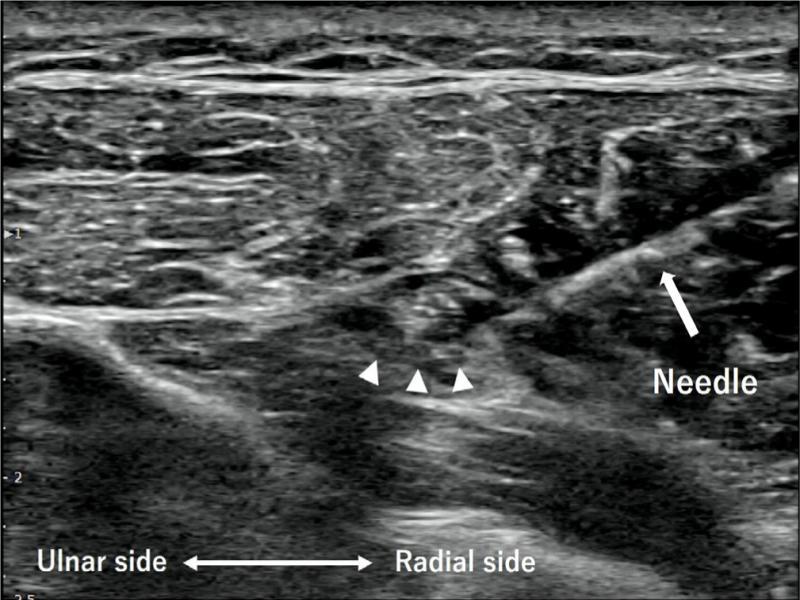

The nerve was identified using ultrasonography, and a 27-gauge needle was guided in real time and in plane until the tip was adjacent to the nerve. We injected 0.1% lidocaine solution (1 mL of 1% lidocaine combined with 9 mL of saline) until the nerve was surrounded with fluid and was separated from the surrounding tissue. Approximately 5 mL of 0.1% lidocaine solution was injected (Fig. 3). One week after the hydrodissection, the patient reported an improvement in extension of the index finger; however, there was little improvement in his thumb. Since the symptoms had improved, we performed perineural hydrodissection four times, every other week. Eight weeks after the first hydrodissection, thumb extension was found to have slightly improved. Ten weeks after the first hydrodissection, the patient regained almost full range of motion in his thumb. Fifteen weeks after the first hydrodissection, there was no restriction in his thumb and fingers movement. The active thumb and index finger extension were identical to the contralateral side. Ultrasonography revealed that multiple stenotic lesions were slightly improved (Fig. 4). At one-year follow-up, his thumb and fingers were still in a good condition (Fig. 5), and ultrasonography revealed no recurrence of PIN stenosis. Electromyography and a nerve conduction study recorded the compound muscle action potential from the extensor indicis proprius muscle, and the motor nerve conduction velocity was normal (54.8 m/s).

Fig. 3.

A transverse image at the level of the distal end of the supinator muscle. A 27-gauge needle tip was guided adjacent to the PIN nerve and approximately 5 mL of 0.1% lidocaine solution was injected around the nerve (arrowheads). Hyperechoic bands were detached from the nerve